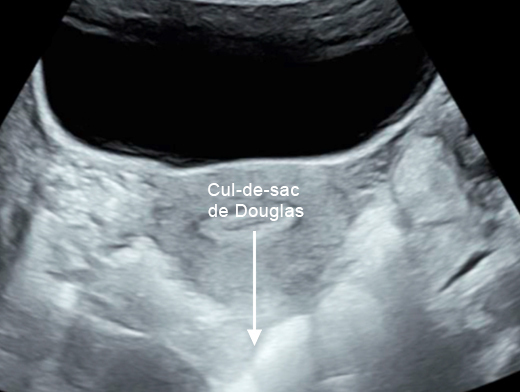

Concernant l’hématome sous-capsulaire du foie : Tableau 3 (Rodolphe Matias de Sousa, La Revue du Praticien) Concernant l’échographie transabdominale à la recherche d’un hémopéritoine :on regarde deux espaces, le cul-de-sac de Douglas entre l’utérus et le rectum, et l’espace de Morrison entre le foie et le rein. Figure 3a (Rodolphe Matias de Sousa, La Revue du Praticien)Figure 3b (Rodolphe Matias de Sousa, La Revue du Praticien)Figure 3c (Rodolphe Matias de Sousa, La Revue du Praticien) Pour rappel, concernant l’échographie en gynécologie : Figure 4a (Rodolphe Matias de Sousa, La Revue du Praticien)Figure 4b (Rodolphe Matias de Sousa, La Revue du Praticien)Figure 4c (Rodolphe Matias de Sousa, La Revue du Praticien)Figure 4d (Rodolphe Matias de Sousa, La Revue du Praticien)Figure 4e (Rodolphe Matias de Sousa, La Revue du Praticien)Figure 4f (Rodolphe Matias de Sousa, La Revue du Praticien)Figure 4g (Rodolphe Matias de Sousa, La Revue du Praticien)Figure 4h (Rodolphe Matias de Sousa, La Revue du Praticien)Figure 4i (Rodolphe Matias de Sousa, La Revue du Praticien)